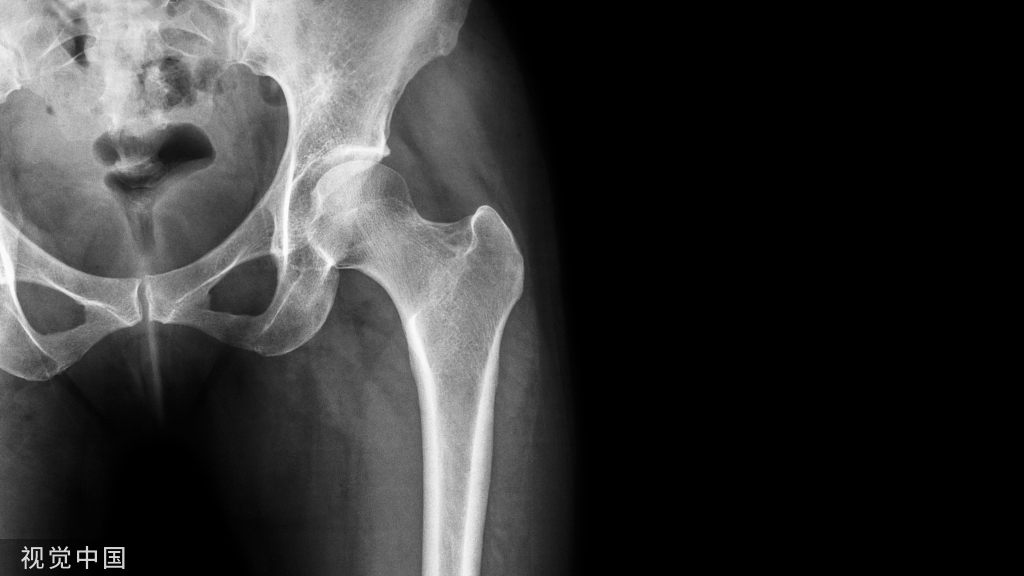

平片二

X 线平片上表现为伴有清晰薄层硬化缘的环形(囊状)透亮区,CT 上表现为圆形 或类圆形的皮质下局灶性骨质缺损,周围见薄层硬化带环绕 边缘锐利,部分较大病灶在病灶层面或上下相邻 、层面上前方显示皮质与病灶相通的局部裂隙样缺损病灶,最大径线通常小于 10 mm;MRI 示病灶在 T1WI 上呈低信号,在 T2WI 上呈均匀或不均匀高信号。